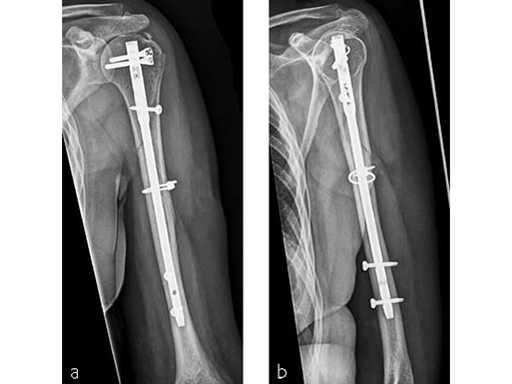

Case 2: Three-part valgus displaced fracture of the proximal humerus in a 63-year-old man.

The tuberosities have been reduced and fixed using intertubercular sutures (Fig 4). To reconstruct the medial support a calcar screw has been used. This determines the height of the nail. Therefore a 1 cm end cap has been used to get support for the proximal end of the nail in the part of the bone with the best bone quality.